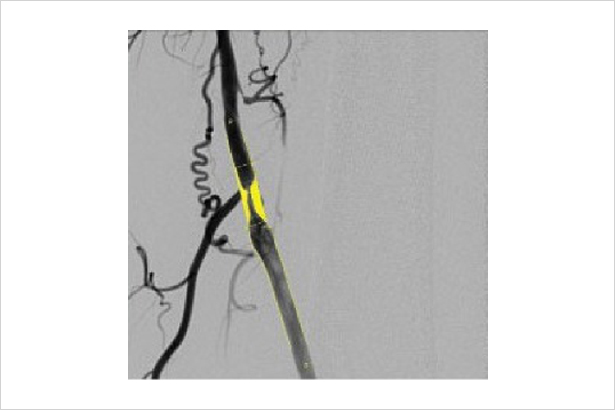

實時顯示患者皮膚接受輻射劑量區域分布情況,供醫生參考患者皮膚劑量水平,進而改善醫生操作流程和使用習慣